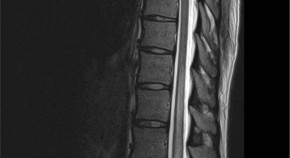

Spinal cord ischaemia is a rare complication following the gluteal injection of Benzathine benzylpenicillin. The hypothesis is embolization of the Penicillin products retrogradely through the Superior gluteal artery and cause occlusion of the vasculature that supply the spinal cord. This article includes literature review of the hypothesis behind the Spinal cord ischaemia and highlights the previous cases reported.